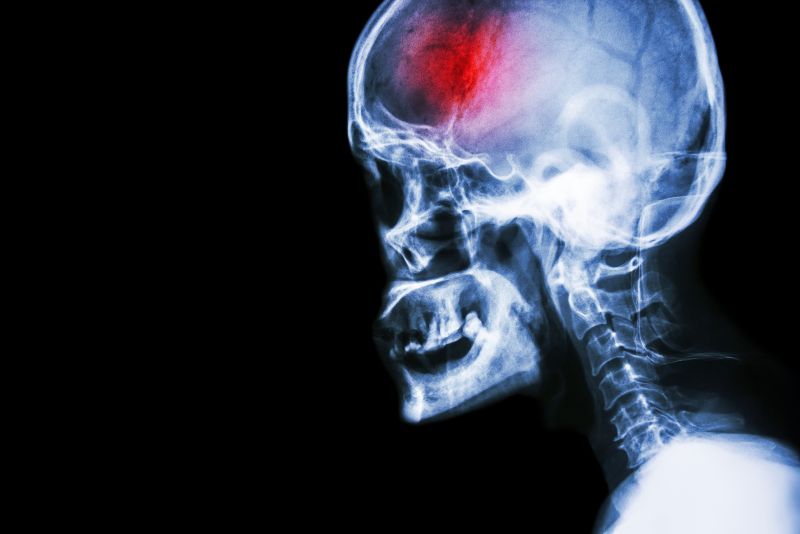

Conclusion

Head X-rayA stroke is a serious medical emergency that requires immediate action in order to achieve the best eventual outcomes. Early medical intervention, as well as early, consistent and ongoing rehabilitation will positively affect your long term capabilities.  Physical therapy services at FYZICAL Upper Arlington can assist you to recover from your stroke and regain your maximum potential.